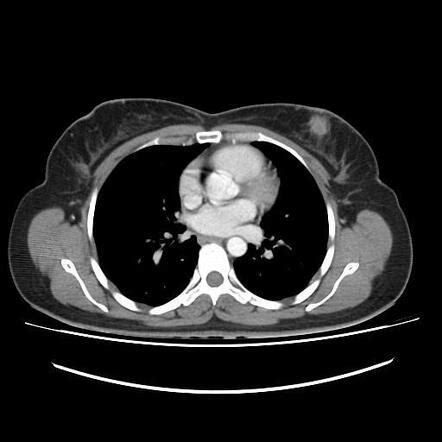

Spotting metastatic triple-negative breast cancer (mTNBC) isn’t always straightforward, as its symptoms can be varied and sometimes mimic other conditions. Generally, when breast cancer becomes metastatic, it means it has spread beyond the breast and the nearby lymph nodes. So, symptoms can appear in different parts of the body where the cancer has traveled. If the cancer has spread to the lungs , you might experience persistent coughing, shortness of breath, or chest pain. Liver metastases can show up as jaundice (yellowing of the skin and eyes), abdominal pain or swelling, nausea, or loss of appetite. Bone metastases are often characterized by bone pain, which can be constant and severe, and sometimes pathological fractures, where a bone breaks with minimal or no trauma. If the cancer reaches the brain , symptoms can include persistent headaches, blurred vision, dizziness, seizures, or changes in personality or behavior. It’s also possible to have general symptoms like extreme fatigue, unexplained weight loss, or a feeling of being generally unwell. The diagnosis of mTNBC involves a comprehensive approach. It usually starts with a thorough medical history and physical examination. Imaging tests are crucial; these might include CT scans, PET scans, bone scans, or MRIs to detect tumors in other parts of the body and determine the extent of the spread. A biopsy of a suspicious area in another organ is often necessary to confirm that the cancer is indeed breast cancer that has metastasized, and importantly, that it is triple-negative. This involves testing the biopsy sample for ER, PR, and HER2 status. Sometimes, genetic testing of the tumor or blood can provide additional information about specific mutations that might be targetable or indicate inherited predispositions like BRCA mutations. The journey to diagnosis can be stressful, but getting an accurate and timely diagnosis is paramount for developing the most effective treatment plan. Doctors will work diligently to piece together all the information to understand the full picture of the disease.

Guys, let’s talk about the diagnostic process for metastatic triple-negative breast cancer (mTNBC) . When your doctor suspects that your breast cancer might have spread, or if you’re presenting with symptoms that point towards metastasis, a series of tests will be initiated. It’s not just one single test; it’s a whole investigative journey to get a clear picture. First off, they’ll likely start with a physical examination and ask detailed questions about your symptoms and medical history. Then come the imaging studies . These are super important for visualizing what’s going on inside your body. You might undergo a CT scan (Computed Tomography), which uses X-rays to create detailed cross-sectional images of your body. This can help detect tumors in organs like the lungs, liver, or adrenal glands. A bone scan is specifically designed to check if the cancer has spread to your bones. You’ll be injected with a small amount of radioactive material that attaches to areas of bone activity, and a special camera will detect where this material has gathered, highlighting potential metastatic sites. A PET scan (Positron Emission Tomography) is another powerful tool. It uses a radioactive tracer that your body absorbs, and cancer cells tend to absorb more of this tracer, making them light up on the scan. PET scans can help identify cancer throughout the body. An MRI (Magnetic Resonance Imaging) might be used, especially if brain or bone involvement is suspected, as it provides very detailed images of soft tissues and bones. If these scans show suspicious areas, the next crucial step is a biopsy . This is the definitive way to confirm cancer and its type. A small sample of tissue is taken from the suspected metastatic site (e.g., a nodule in the lung, a lesion in the liver or bone). This sample is then sent to a lab for analysis. Pathologists will examine the cells under a microscope and perform crucial tests to determine if the cancer cells are indeed from the breast and, critically, if they are triple-negative (negative for ER, PR, and HER2). Sometimes, a biopsy of the original breast tumor might be redone or reviewed to ensure the triple-negative status is accurate. In some cases, liquid biopsies – analyzing cancer DNA shed into the blood – are becoming more common and can provide insights into the cancer’s genetic makeup and mutations, which might guide treatment decisions. Genetic counseling and testing may also be recommended, especially if there’s a family history of breast or ovarian cancer or if BRCA mutations are suspected, as these can impact treatment options and family planning. It’s a thorough process, and while it can feel overwhelming, remember that each step is designed to gather the vital information needed to fight this disease effectively. It’s all about getting the right information to the right people to make the best treatment choices.